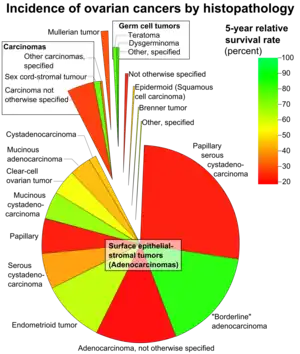

Ovarian cancers in women aged 20+, with area representing relative incidence and color representing 5-year relative survival rate.[1] Papillary serous cystadenocarcinoma is labeled at center right.